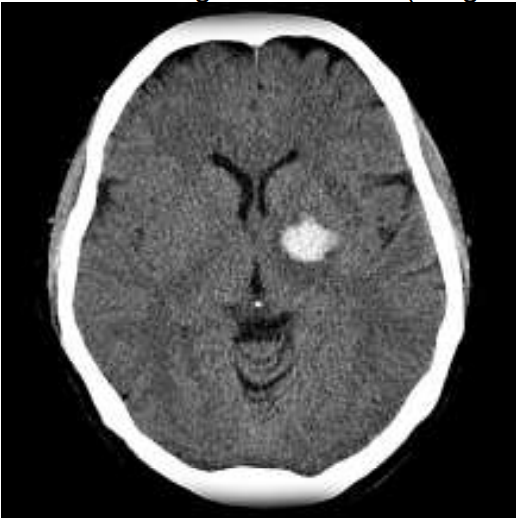

Mulher de 54 anos, tabagista, com diagnóstico de hipertensão e diabetes prévio, cursou de forma súbita com hemiparesia proporcionada completa à direita. Procurou serviço de emergência, vigil, consciente, disártrica, desorientada em tempo e orientada em espaço, obedecendo comandos, sensibilidade, coordenação sem alterações, NIHSS 10. Após 1h30 do ictus realizou tomografia de crânio (imagem).

Tomografia de crânio com volume estimado do hematoma menor que 30ml

Sobre o quadro da paciente, assinale a alternativa correta.